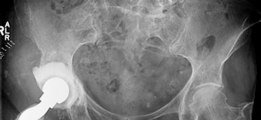

Main steps : (1) Prostalac removal. (2) Preparation of the anatomic acetabulum with reamers to determine the cup size. (3) Size acetabular rim defect and use reamers to size defect and prepare a smooth surface. (4) Place augment with provisional pins with the trial cup in place. (5) Add screws to augment. (6) Apply cement to the augment and impact acetabular component. (7) Prepare femur and insert stem (Figs. 19.15 and 19.16).

--- Fig. 19.15 Intraoperative view of the acetabular rim defect and augment with cement at the component interface. Modular Wagner femoral revision stem with severe proximal femoral bone loss #### Intraoperative Challenges

Postoperative Radiographs

(Fig. 19.16)